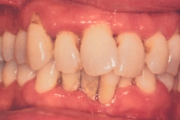

Krooniline parodontiit

Krooniline parodontiit on mikroobide poolt põhjustatud hammaste tugikudede põletik, mille tulemusena tekib progresseeruv alveolaarluu (nähtav röntgenograamil) ja periodontaalligamendi destruktsioon, igemetaskute moodustumine, igeme retsessioon või mõlemad kahjustused kombineeritult. Loe edasi »

- igemed veritsevad (19)

- igemed punetavad (21)

- ige on paistes (mädapunn)

- igemed on tursunud/vohavad (17)

- igemepiir on taandunud (3)

- igemepealne hambakivi (5)

- igemealune hambakivi (4)